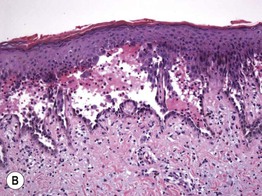

Fig. 1.13 Intraepidermal vesiculobullous dermatosis, acantholytic type. A Pemphigus vulgaris with flaccid bullae and erosions. B The keratinocytes within the lower epidermis have lost their intercellular attachments and have separated from one another, resulting in an intraepidermal blister. A, Courtesy, Louis A. Fragola, Jr., MD; B, Courtesy, Carlo F. Tomasini, MD.